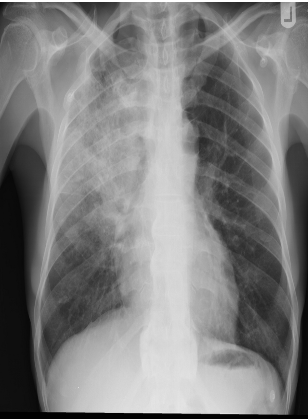

- Bacterial pneumonia:

- Lobar consolidation (air bronchogram) occasionally with parapneumonic effusion. Pneumatocoele and abscesses suggest staphylococcal pneumonia

Right lower lobe consolidation in a patient with bacterial pneumonia.